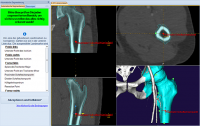

Giao diện của Phần mềm MediCAD dễ hiểu, rõ ràng, dễ thao tác. Các bác sĩ có thể tập trung, phóng to các bộ phận quan trọng trong việc lên kế hoạch điều trị bệnh.

Công nghệ 3D đảm bảo chính xác trong quá trình phẫu thuật, đây là công nghệ tiên tiến nhất đảm bảo về độ an toàn cũng như thành công của ca phẫu thuật thẩm mỹ về hàm mặt.